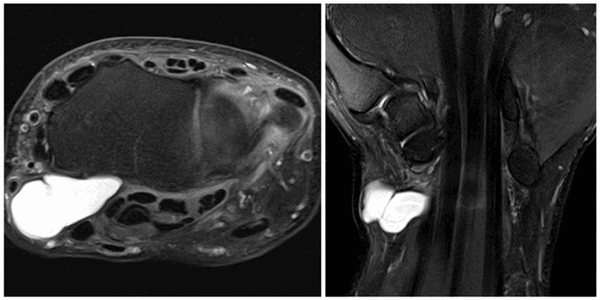

Как выглядит ганглиевая киста на МРТ? Это одно- или многокамерное кистозное образование с равномерно гипоинтенсивным сигналом на Т1 ВИ, гиперинтенсивным сигналом на Т2 ВИ и STIR, накапливающее контраст на основе гадолиния в виде «ободка». В некоторых случаях обнаруживается также повреждение сухожилия вблизи кисты.

На УЗИ ганглий выглядит как одно- или многокамерное образование с тонким «ободком» и множественными перегородками, чаще всего анэхогенное, реже с эхогенными включениями. Может обнаруживаться также акустическое усиление. Для поиска кровотока в образовании и признаков, позволяющих отличить ганглий от опухоли, используется цветовая или энергетическая допплерография. Ультрасонография, допплерография, МРТ — наилучшие методы визуализации сухожильного ганглия.